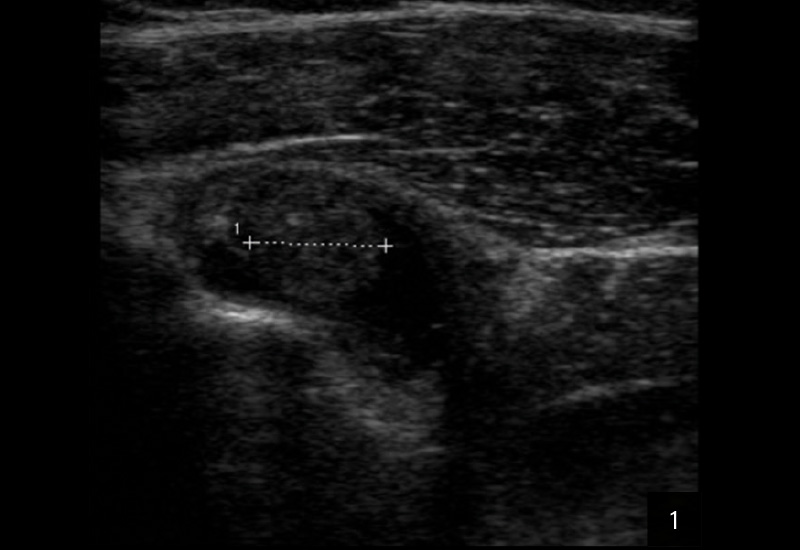

DIAGNOSE: TENOSYNOVITIS DER LANGEN BIZEPSSEHNE BEI RA

Die Sonografie gilt als erstes bildgebendes Verfahren hoher Wertigkeit bei der Diagnose einer Tenosynovitis der langen Bizepssehne, da sie dynamische Untersuchungen ermöglicht und periphere sowie intraartikuläre Abschnitte zuverlässig darstellt. Typische sonografische Kriterien umfassen eine Sehnenschwellung mit echoarmen Arealen, umgebende Flüssigkeitsansammlungen in der Sehnenscheide (Halo-Phänomen), synoviale Verdickungen und erhöhten Dopplerfluss als Hinweis auf Hypervaskularisation. Die Methode ist untersucherabhängig, bietet jedoch eine hohe Sensitivität (50–96 %) und Spezifität (bis 100 %) für Instabilitäten, Luxationen oder Rupturen, insbesondere durch Provokation in Außenrotation.